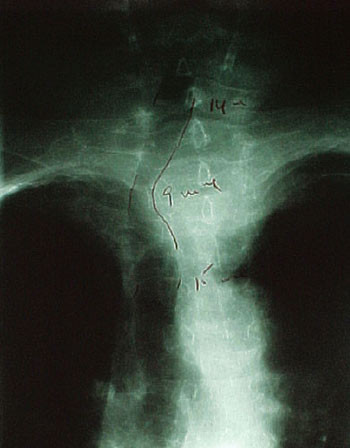

Ved undersøkelse virket pasienten eutyreot, hadde ikke takypné, men inspiratorisk stridor. Strumaet var betydelig, beveget seg litt ved svelging og var forholdsvis mykt og uømfintlig. CT av halsen og mediastinum viste betydelig cervikalt og intratorakalt struma med tracheadeviasjon og betydelig lumenkompresjon (fig 2).

På bakgrunn av hennes store, langsomt voksende struma, betydelige tracheakompresjon og intermitterende symptomer i form av dyspné, fikk hun fire doser radiojod (4 x 800 MBq), med intervaller på ca. en måned. Rundt fire måneder etter siste radiojodbehandling var den cervikale strumadelen mindre, og det var betydelig bedring av de respiratoriske symptomer og funn.

Bildeundersøkelser og cytologi

Røntgen trachea, røntgen thorax eller bedre CT thorax (fig 2, fig 3) eller MR-undersøkelse kan avdekke og kvantitere intratorakalt struma, tracheadeviasjon eller -kompresjon. MR er mest nøyaktig, men også mest ressurskrevende. Med MR unngår man å gi jodholdig kontrast som kan gi kontrastmiddelindusert hypertyreose ved preeksisterende jodmangel og forstyrre videre nukleærmedisinsk diagnostikk og terapi i flere uker til måneder (17). Konvensjonell røntgen, CT eller MR er ikke indisert ved ukomplisert, lite struma eller ved knuter i en ellers upåfallende thyreoidea.